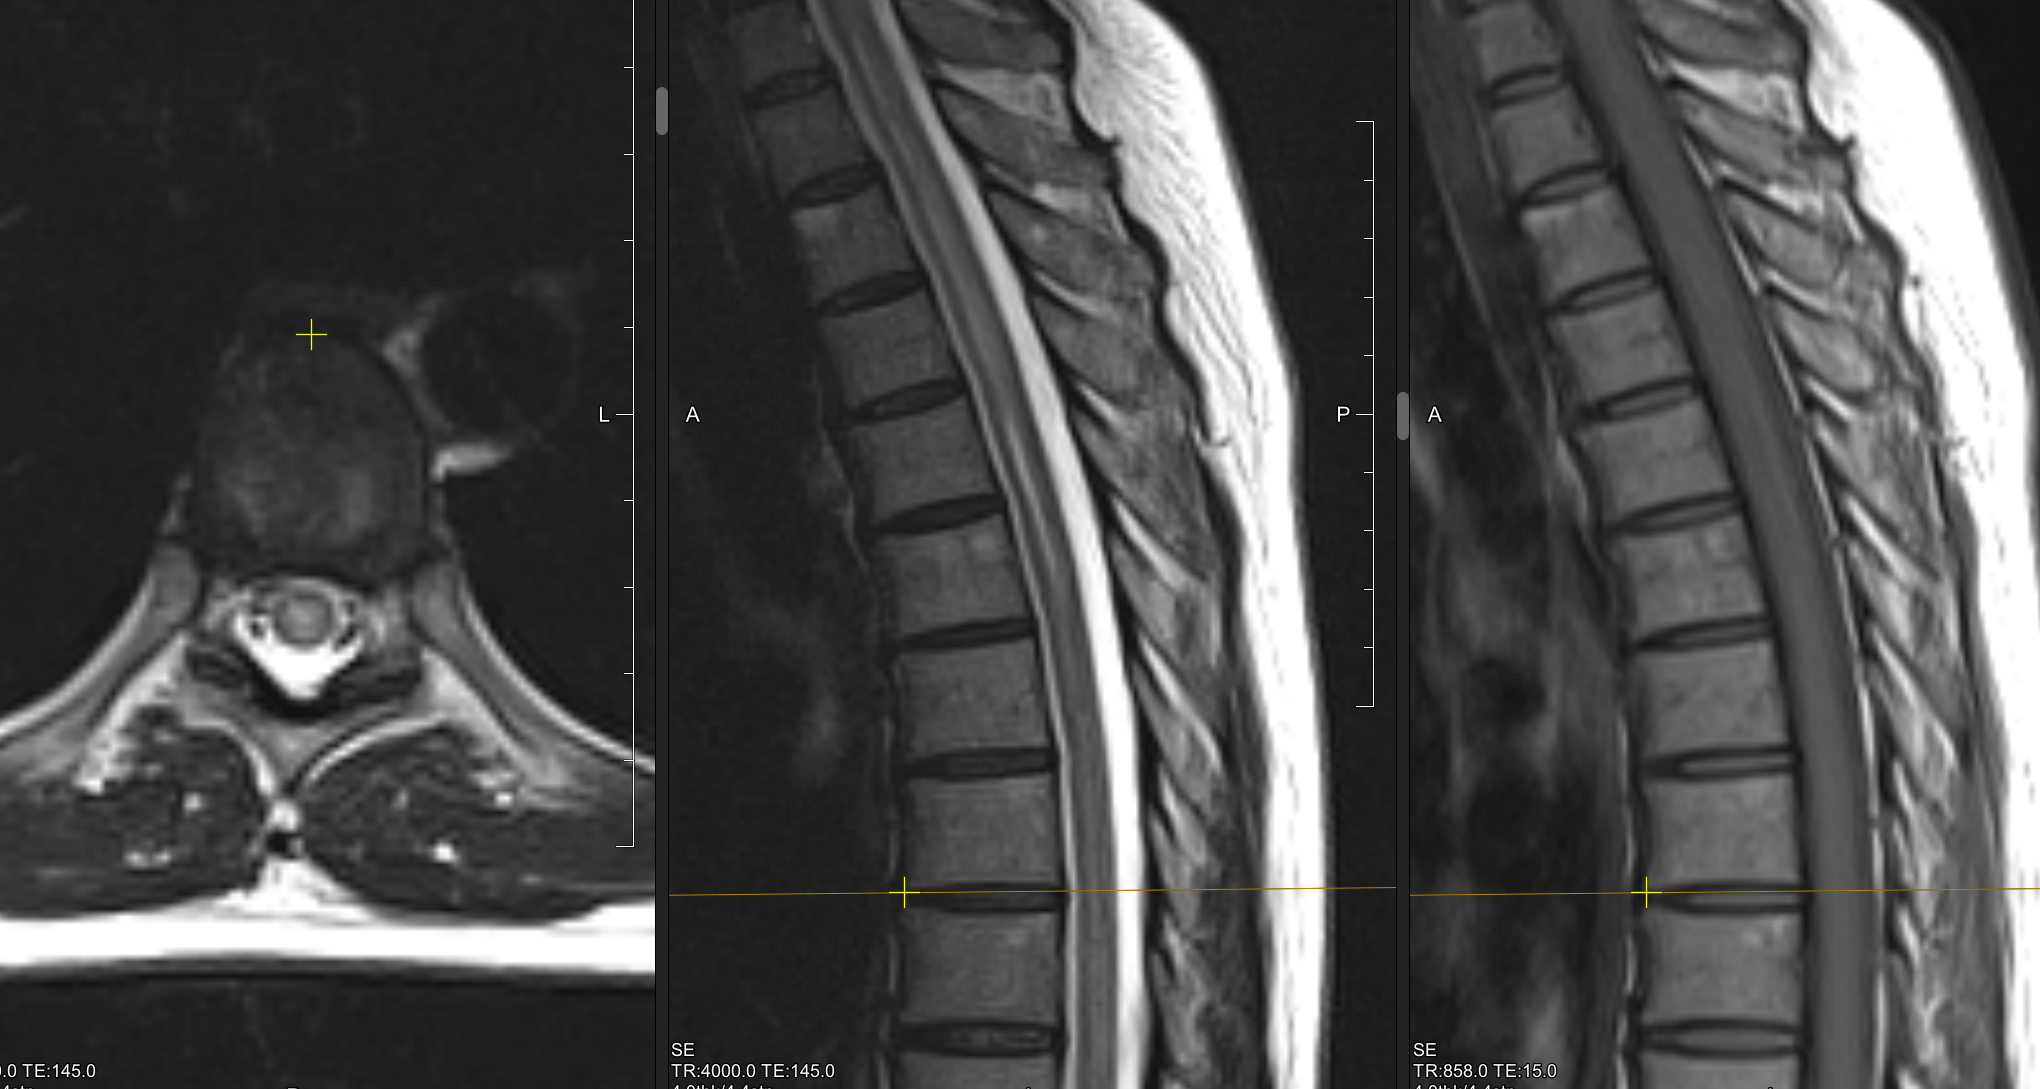

Сирингомиелия что

Сирингомиелия что 111 фотографий